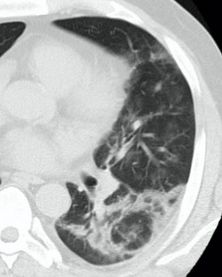

Здоровье детей: признаки инфекционного бронхиолита